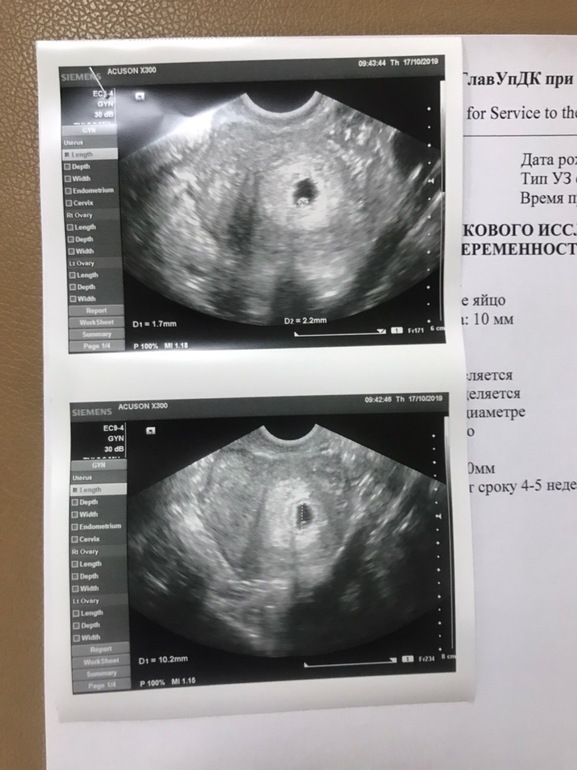

Первое узи,5 недель

на узи ПЯ 10мм,желточный мешочек 2 мм.По месячным срок 5 недель 2 дня)Предыдущие мои мельче были на этом сроке)Всегда делаю узи на 9-10ДЗ)